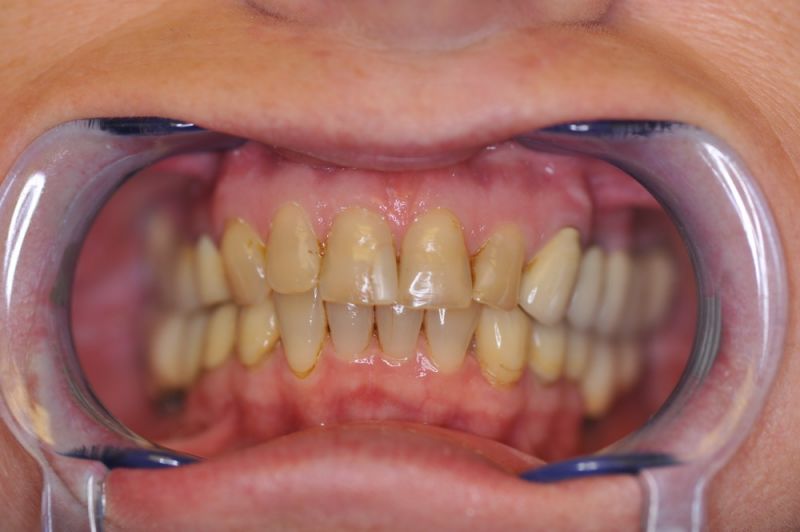

Schwierigster Fall aller Zeiten, praktisch beschwerdefrei. Patientin glücklich!

Es war eine Kombination aus Schmerzen bis an die Suizidgrenze, beschränkten wirtschaftlichen Möglichkeiten, sehr stark eingeschränkten Möglichkeiten der für Implantate zur Verfügung stehenden Knochenverhältnisse in einem stark atrophierten Unterkieferseitenzahnbereich und zudem dann auch noch durch auftretenden Problemen bei der Implantatinsertion und nachfolgenden Versorgung der Implantate.

Die Problematik der Implantatversorgungen kann man in einer Analogie folgendermaßen darstellen. Die räumlich beengten Zustände gleichen dem Tanz eines Paares auf einer Briefmarke, und der gleichzeitigen Schritt- und Fusshaltung, dass beim Tanzen die Schuhe geputzt werden können!